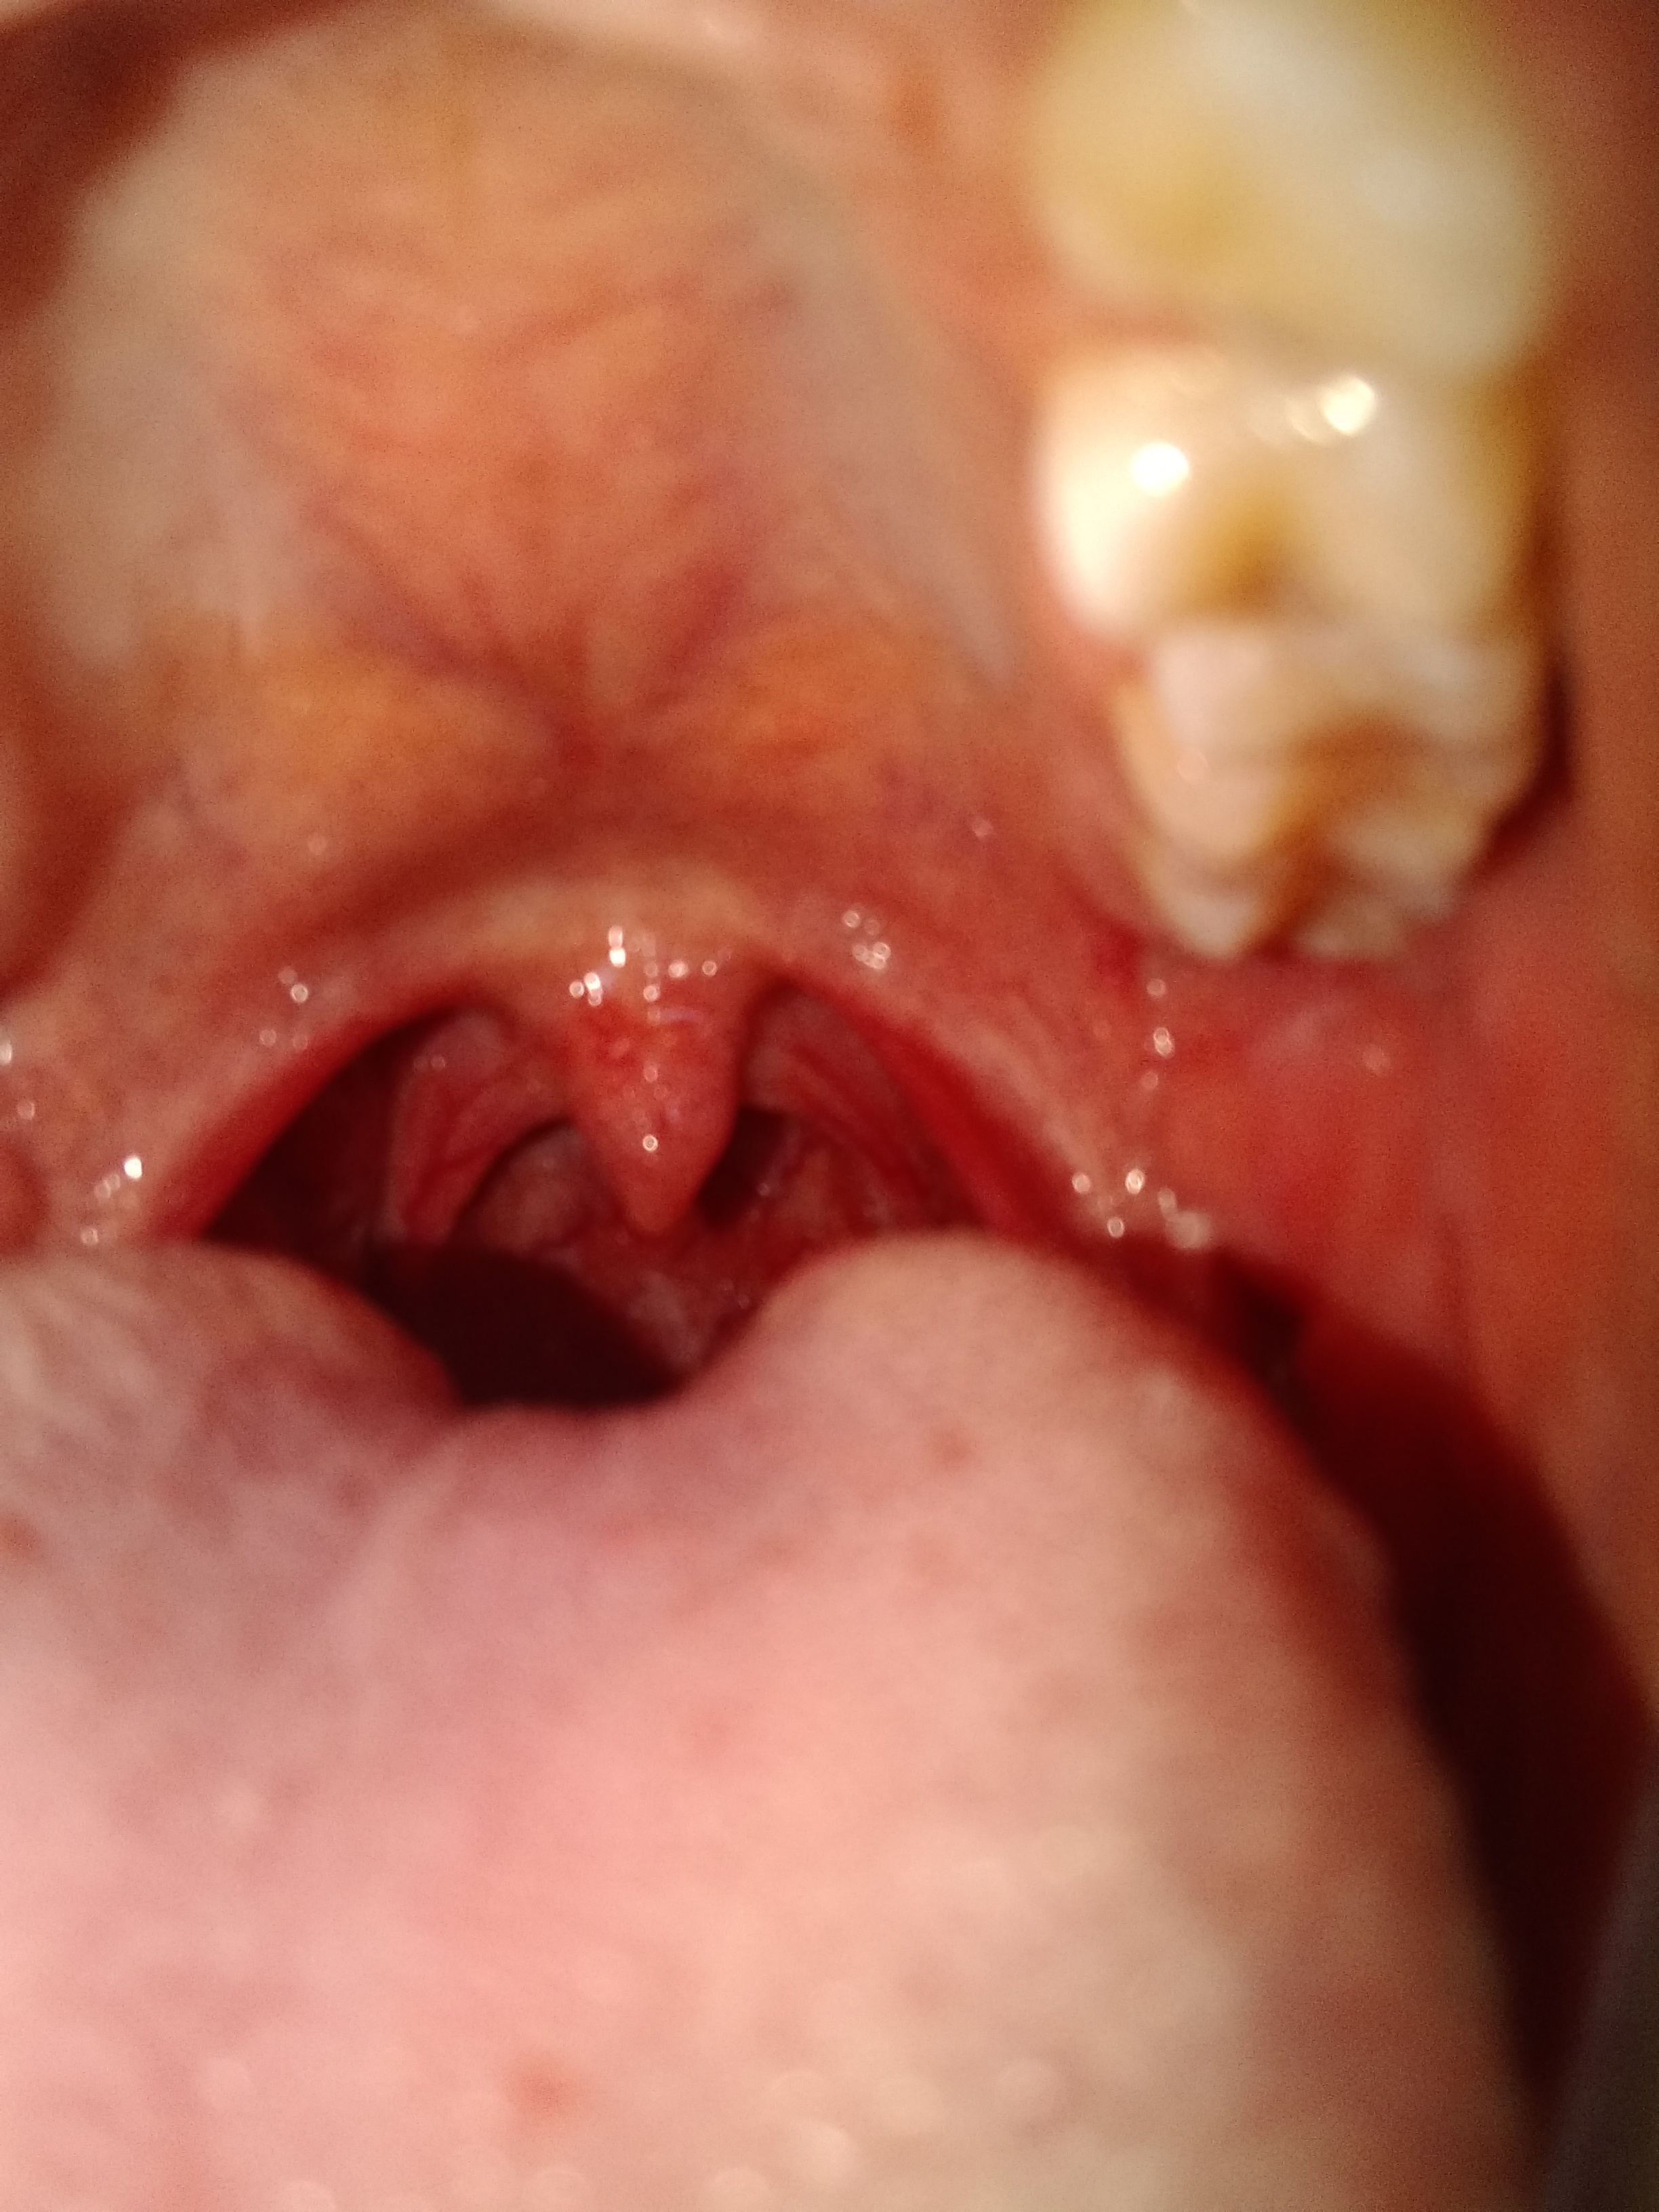

Tuve sexo oral homosexual pero al día siguiente amanecí con ruidos intestinales fuertes, de ahí molestias en la garganta, note que me salieron como puntos rojos en la garganta estoy un poco asustado

Alguien me puede orientar ? Ahora tengo como un punto negro en la ensia como con sangre